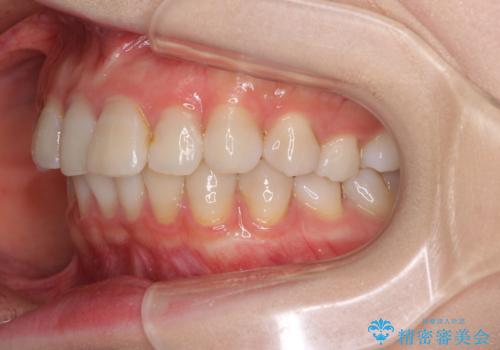

前歯の突出感とデコボコをインビザライン矯正で改善

- 上下前歯の突出感とデコボコを気にして来院された患者様です。

インビザラインによる上下歯列の側方拡大と後方移動、IPR(歯と歯の間を削る)にるスペースの獲得により歯列を整えることとしました。

骨格的な左右差があったため、上下の正中を合わせることができませんでした。

骨格の差は改善できないため、奥歯の咬み合わせに物足りなさを感じましたが、奥歯の咬み合わせによる不自由はなく、口元の突出感も改善することができました。